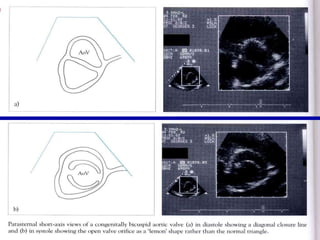

Ecocardiogram a : Puede evitar el cateterismo en casos característicos Es de importancia para diagnosticar  Aorta bivalva.

ECO: Aorta bivalva

Ecocardiogram a :Puede evitar el cateterismo en casos característicos Es de importancia para diagnosticar Aorta bivalva.